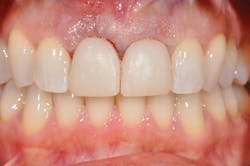

Figure 2: Prior to procedures, teeth appeared healthy with no clinical signs of trauma.

Figure 6: Immediate-load temporaries are finished.

Through the entire procedure I was completely comfortable physically-no pain, only pressure. Truth is, when there is a gaping hole in the front of your mouth, it's a crazy feeling every time you swallow. My mouth was numb but my tongue could totally feel the absence, and my brain could imagine a train driving through this giant gap. Temporaries going in, shade chosen ... in hindsight recommend that your patients whiten to their desired shade in advance if there is time because this will be a forever shade (see Figure 6). I was numb for several hours, took three ibuprofen, and antibiotics which I had started two days prior. That evening, brushing was frightening but I felt nothing, literally nothing! The false tooth and tissue and my entire premaxilla was numb, void of all feeling. While it meant pain meds were unnecessary, it was disconcerting to have nothing there. I chose to use only plastic cups and silverware and eat completely soft foods. The temporaries are for appearance only, and mine were stunning, but they are not, not, not to be used for biting. This time is for healing and permanent restorations are not scheduled for 12-16 weeks.